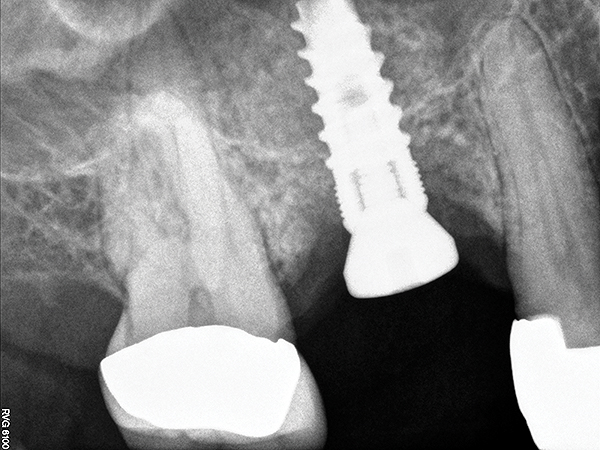

The implant is then delivered and should be well stabilized in the bone. If there is any mobility of the implant, it can either be placed a little deeper (if there is enough native bone) or the implant can be removed and the procedure aborted, in which case it would be a two-stage procedure. This should rarely occur with the tapered designed implant, even with only 2 mm of native bone. Using a bone-level platform-shifting implant (or a tissue-level designed implant) is critical, as the hard and soft tissue will establish a biologic width. If an external hex type of implant is used and the shoulder is placed at the bone level, an expected bone loss of 1.5 mm to 2 mm will occur.24 Figure 10 shows proper bone-level implant depth placement with a platform-shifting design. In this case, a 3-mm healing abutment was placed at the time of surgery to avoid a secondary uncovering surgery, but an implant-level healing abutment could have been placed instead. As can be seen, there was only about 2 mm to 3 mm of native bone height. The membrane was raised about 8 mm to 9 mm. Comparing the radiograph on the day of surgery (Figure 10) to the 6-month postoperative radiograph (Figure 11) shows no loss of native bone, as well as the positive change in appearance of the grafted bone. The 3.5-month CBCT scan (Figure 12) shows good healing of the bone with no coronal bone loss. With minimal native bone present, as in this case, the use of a non-platform-shifting or non-tissue-level implant design could be problematic. After 1.5 mm to 2 mm of crestal bone loss, an external hex designed implant could develop instability with possible implant failure. If a non-tapered implant is used and bone loss occurs during healing, migration of the implant into the sinus could potentially occur. The surgeon can use either a healing abutment or implant-level closure screw over the implant shoulder. With patients who tend to use their tongues to explore or play with the area, or if the area is under a removable partial denture, a closure screw is recommended.

Fig 10. Radiograph of implant No. 3 and sinus augmentation, day of placement. There is about 2 mm to 3 mm of native bone, and the sinus has been raised about 8 mm to 9 mm.

Figure 10

Fig 11. 7-month postoperative radiograph of the restored implant No. 3.

Figure 11

Fig 12. CBCT scan (Kodak 9000D) showing 3.5-month postoperative of implant No. 3 in place. Note homogenous appearance of the bone.

Figure 12